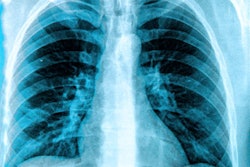

The Targeted Lung Health Check program, which uses CT scans to detect cancer and other diseases sooner, has been open for about a year and has proven its worth. But some are dismissing notifications about the screening, Dr. John Howells, program lead, said in the story.

The program is offered to people between the ages of 55 and 74 who are current or former smokers.